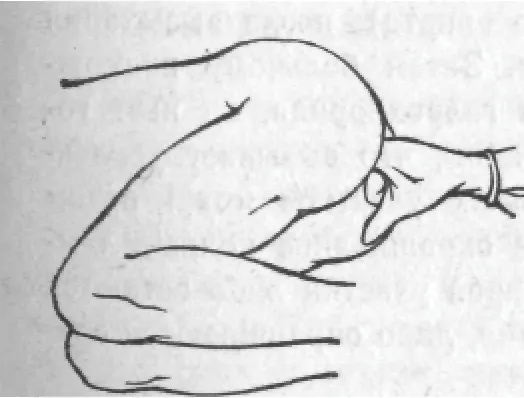

Масаж простати - один з

обов'язкових етапів

«традиційного» способу лікування

простатиту. Процедура принизлива

і болюча (робиться через

анальний отвір). Приймаючи Fenix, її робити не потрібно!

Як і будь-які інші

фізіотерапевтичні

процедури

Масаж простати - один з

обов'язкових етапів

«традиційного» способу лікування

простатиту. Процедура принизлива

і болюча (робиться через

анальний отвір). Приймаючи Fenix, її робити не потрібно!

Як і будь-які інші

фізіотерапевтичні

процедури